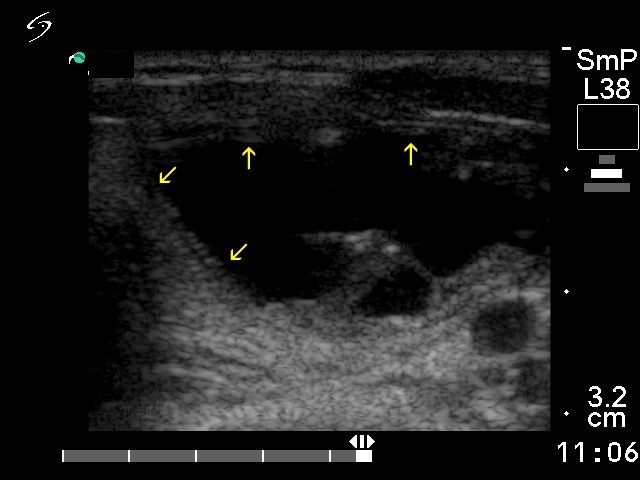

At first sight, both nodules seem to belong to projecting eccentric type. However, solid portions can be observed along the inner wall of the benign lesion (yellow arrows). Therefore, this belongs to the central subtype. The malignant nodule has more projections marked with red arrows.